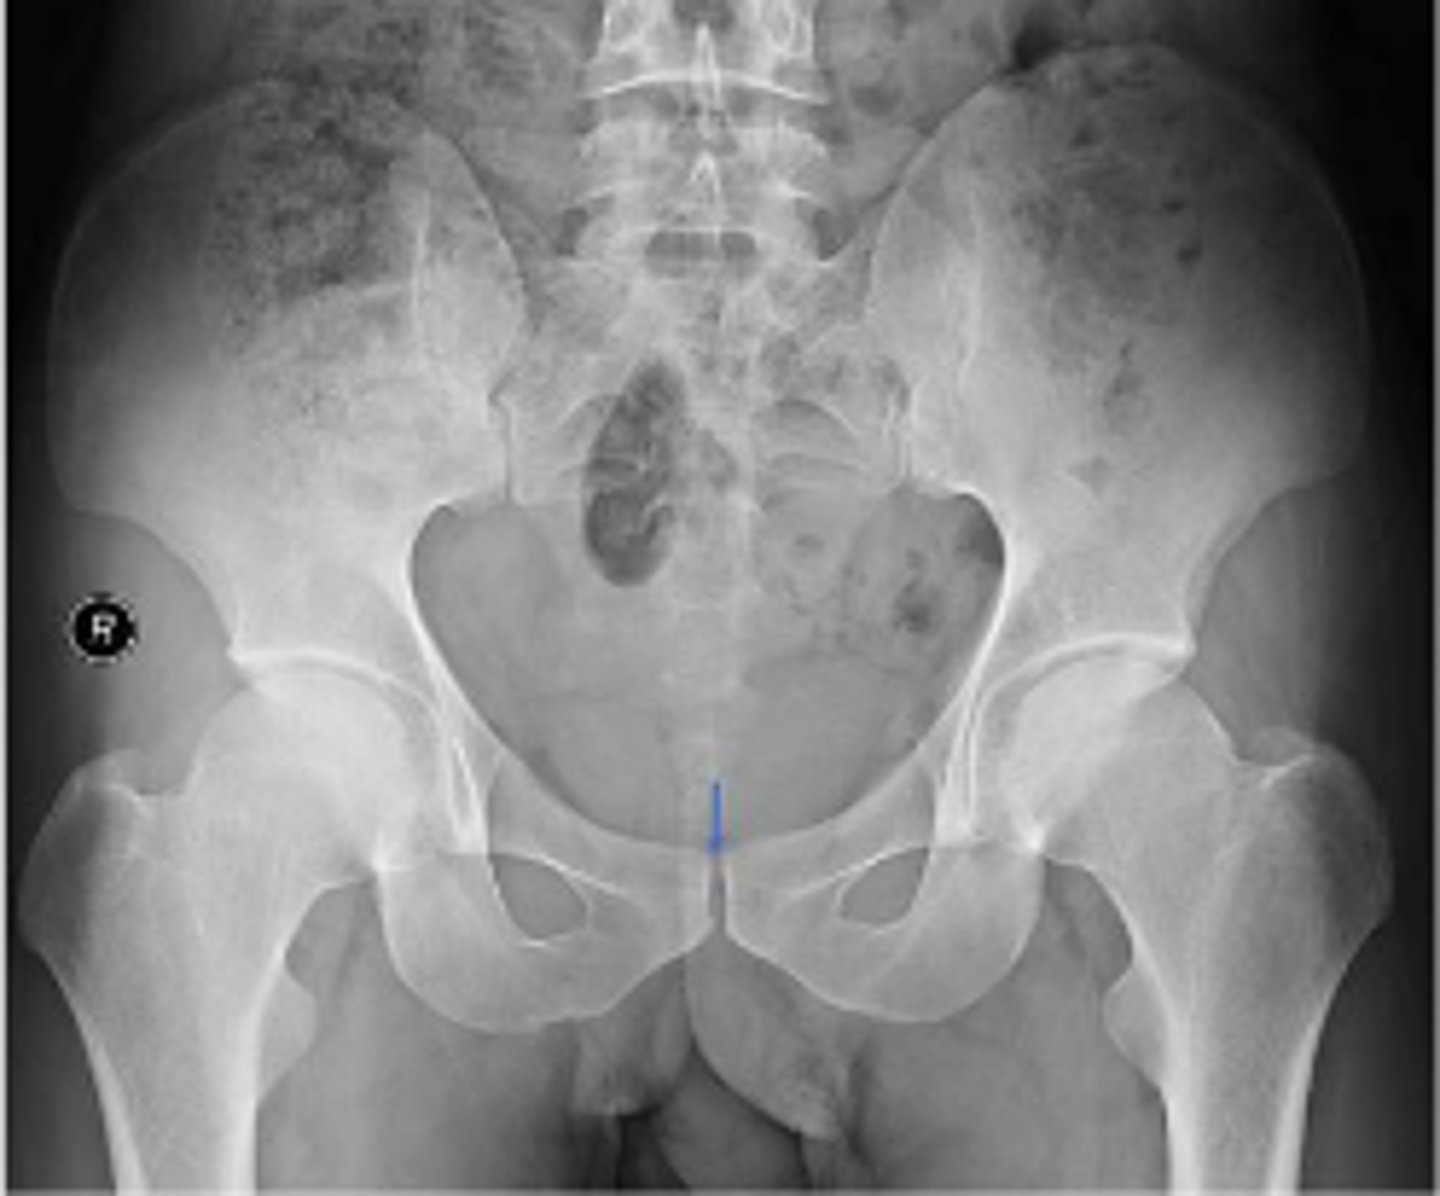

AP pelvis or bilateral hips

What is the name of the radiographic view?

What are the arrows pointing to?

What is the anatomical structure in between the lines?

What is outlined?

What joint space are the arrows pointing to?

What joint space is the arrow pointing to?

Which IVD space is indicated by the arrows?

L4/L5 IVD space